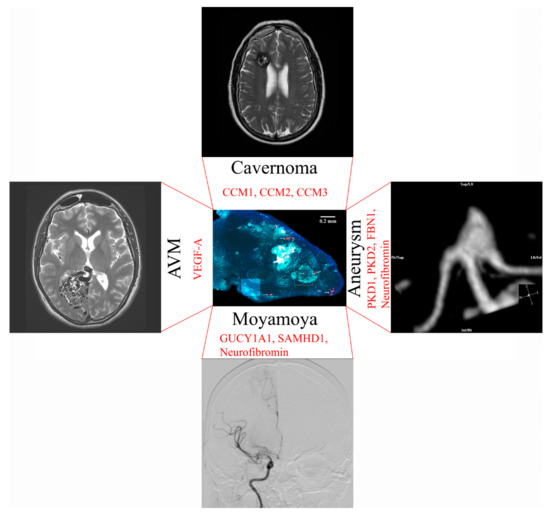

10. Neurosurgical Diseases that Could be Modeled with an Artificial Blood–Brain Barrier

11. Moyamoya Disease

12. Cerebral Aneurysm Formation

13. Modeling of Arteriovenous Malformations

14. Brain Cavernoma Development